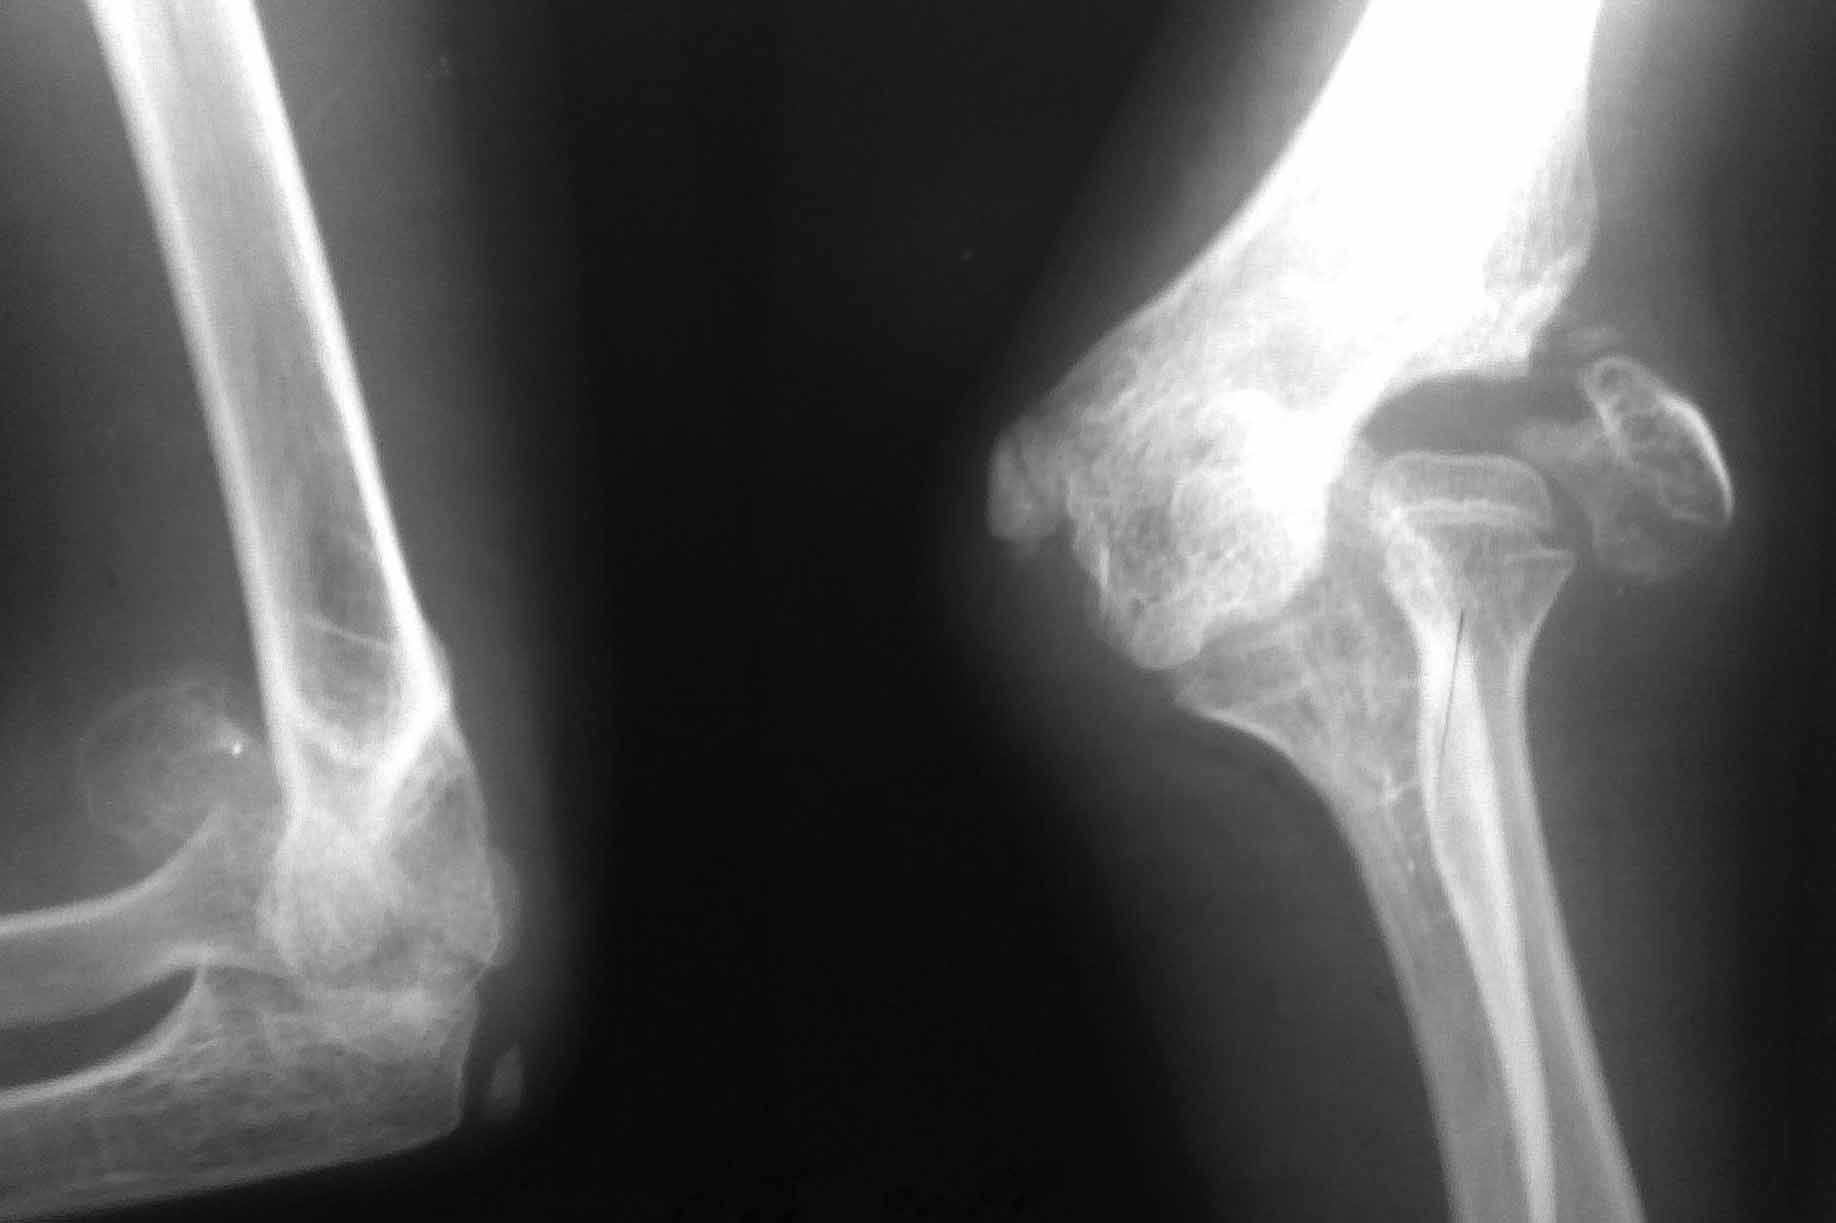

Уважаемые коллеги Очень интересно услышать мнения по тактике лечения пациента 11 лет

DS:Ложный сустав головчатого возвышения правого плеча Вальгусная деформация локтевого

сустава

Пациент 11 лет. Из детского дома. За помощью обратился впервые. Анамнез заболевания собрать

не представляется возможным. Вероятнее всего имел место нелеченный перелом головчатого

возвышения плеча со смещением отломков. Давность травмы неизвестна. Объективно:

Вальгусная деформация локтевого сустава 25-30град. По наружной поверхности пальпируется

тугоподвижный костный фрагмент головчатого возвышения. Функция сустава сохранена в

полном объеме, безболезненна. Рентгенограмма прилагается.